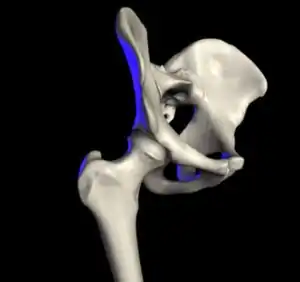

The hip joint is a ball and socket synovial joint formed by the articulation of the rounded head of the femur and the cup-like acetabulum of the pelvis.[5] The socket of the acetabulum is pointing downwards and anterolaterally. The socket is also turned such that the outer edge of its roof is more lateral than outer edge of the floor.[5] It forms the primary connection between the bones of the lower limb and the axial skeleton of the trunk and pelvis. Both joint surfaces are covered with a strong but lubricated layer called articular hyaline cartilage.

The cuplike acetabulum forms at the union of three pelvic bones — the ilium, pubis, and ischium.[6] The Y-shaped growth plate that separates them, the triradiate cartilage, is fused definitively at ages 14–16.[7] It is a special type of spheroidal or ball and socket joint where the roughly spherical femoral head is largely contained within the acetabulum and has an average radius of curvature of 2.5 cm.[8] The acetabulum grasps almost half the femoral ball, a grip deepened by a ring-shaped fibrocartilaginous lip, the acetabular labrum, which extends the joint beyond the equator.[6] The centre of the acetabulum (fovea) does not articulate to anything. Instead, it is lined with fat pad and attached to ligamentum teres. The acetabular labrum is horse-shoe shaped. Its inferior notch is bridged by transverse acetabular ligament.[5] The joint space between the femoral head and the superior acetabulum is normally between 2 and 7 mm.[9]